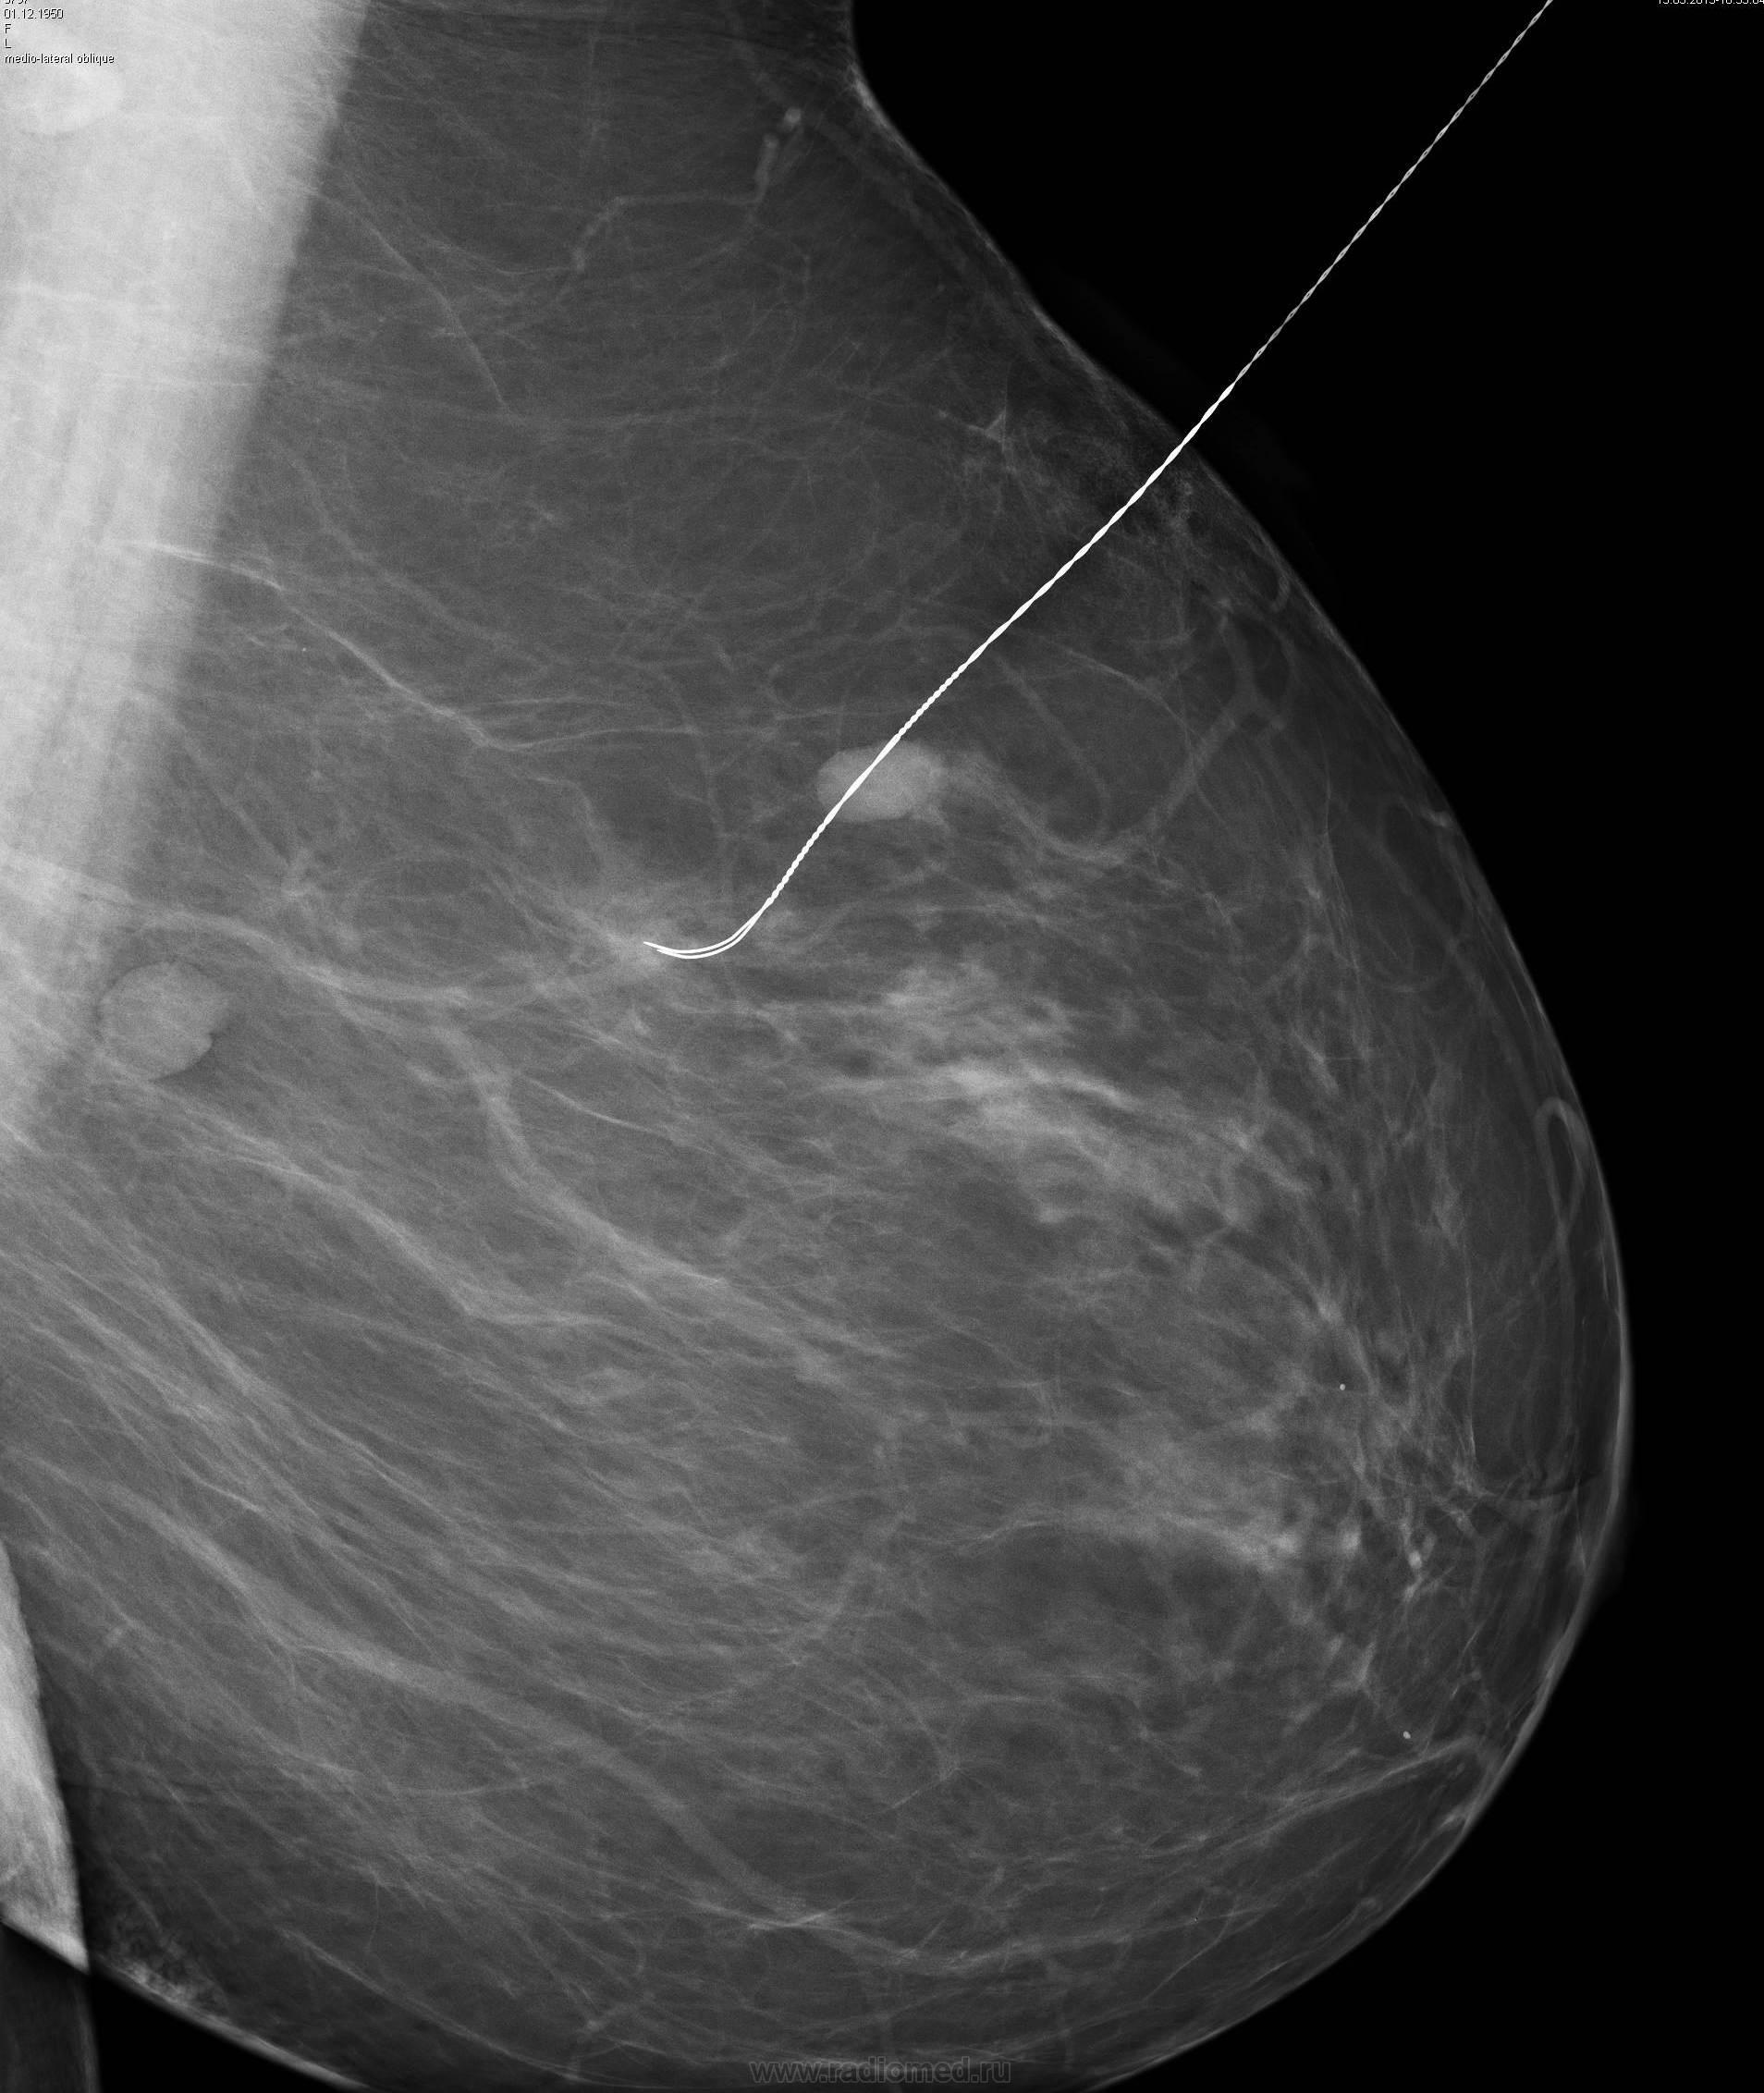

Фиброаденома молочной железы - доброкачественное образование, которое часто встречается у женщин. Оно может быть обнаружено при помощи различных методов диагностики, включая маммографию. Ниже представлены фотографии, помогающие понять, как выглядит данное заболевание.

Операция при фиброаденоме

Маммография и ее роль в диагностике фиброаденомы молочной железы

Маммография - это рентгенологическое исследование молочных желез. Оно позволяет выявить различные изменения в тканях, включая фиброаденому. На маммограммах можно увидеть структурные особенности опухоли и отследить ее динамику во времени.